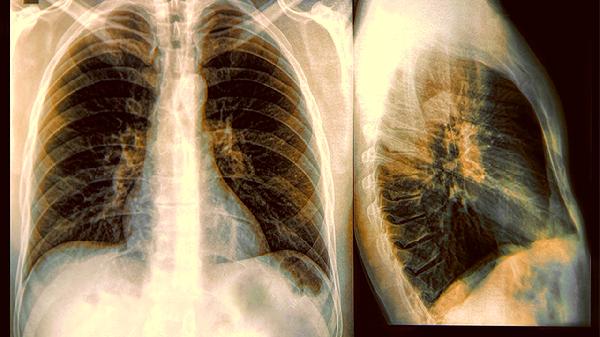

2.影像检查的视觉盲区

CT片上那些毛玻璃样的阴影,可能藏着我们还没发现的浸润成分。就像透过磨砂玻璃看东西,不到手术那一刻,谁都不敢百分百确定病灶的真实性格。